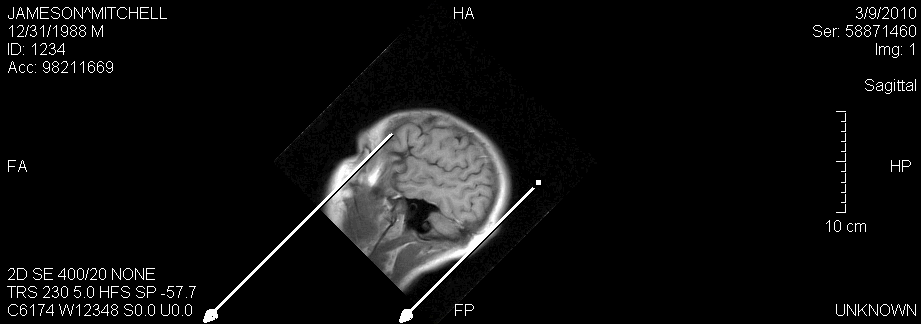

Plumb Lines

The Plumb Line tool from the Annotation Tools toolbar allows the drawing of a line from the selected point on an image vertically down to the bottom of the viewport.

The line ends with a stylized arrow. Multiple plumb lines can be added to an image and if the image is rotated the plumb line will also rotate.